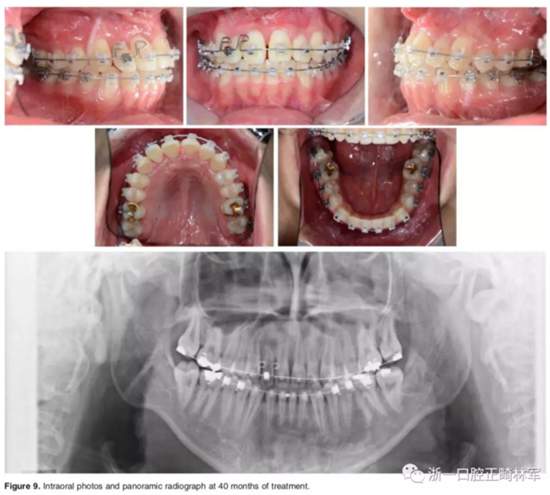

結束階段:

治療40個月后,3顆阻生牙位置已靠攏,繼續(xù)進行排齊。使用高轉(zhuǎn)矩托槽及帶L型曲的0.019*0.025-inch Beta鈦絲對側切牙進行轉(zhuǎn)矩控制,再在雙頜使用0.019*0.025-inch不銹鋼絲進行排齊。矯治結束后,去除托槽、弓絲,雙頜前牙區(qū)粘接保持器。

口外相:前牙易位、阻生均得以正確糾正,牙周組織健康。

口內(nèi)相及模型:I類尖牙、磨牙關系,覆合、覆蓋正常;中切牙與側切牙間有輕微的轉(zhuǎn)矩差;牙齦外形可;此外,在治療期間病人的口腔衛(wèi)生不夠良好,導致幾顆牙齒出現(xiàn)了齲病。

影像學:頭顱側位片示:矢狀向和垂直向骨骼發(fā)生變化(ANB角,3°;SN-MP,51°);上頜切牙略前傾(U1-SN,106°),與下頜切牙一致(IMPA,75°);病人的面部輪廓得以保持。全景片示:由于牙齒萌出,上前牙區(qū)垂直向牙槽骨水平增加;雖然前牙牙根較彎曲,但其平行度仍可,且無明顯的牙根吸收。CBCT示:前牙唇側骨質(zhì)連續(xù)性改善,牙根唇側支持組織變好,牙槽骨高度、厚度均有增加,但轉(zhuǎn)矩的改變一定程度上導致了局部應力的增大。